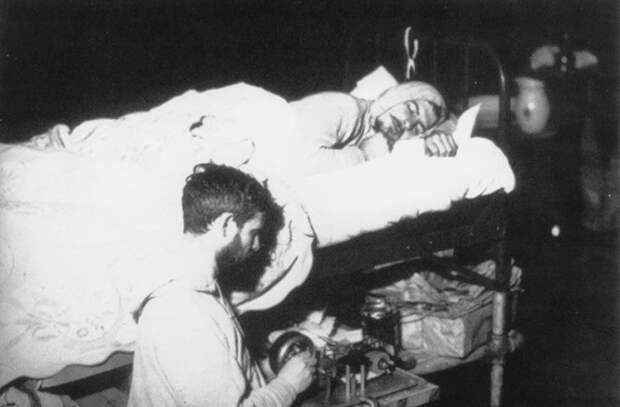

Клейтман проводит эксперимент

Карьера американского нейрофизиолога Натаниэла Клейтмана тоже была наполнена многочисленными экспериментами над собой. Этому человеку, которого в научных кругах называют не иначе как «отцом исследования сна», мы обязаны знаниями о биологических ритмах, фазах сна, а также последствиях его недостатка.

180 часов бодрствуя смог продержаться Клейтман с целью проверки взаимосвязи между депривацией сна и умственной деятельностью. Как было доказано в ходе опыта, нехватка сна не просто влечет за собой ухудшение функционирования мозга, но и способна вызвать галлюциногенные видения и состояние бреда.

А 32 дня, проведенные в Мамонтовой пещере Кентукки, в условиях отсутствия естественного света и сигналов извне, легли в основу изучения влияния окружающей среды на биологические ритмы человека. Клейтман использовал в качестве подопытного не только себя, но и свою семью, родственников и знакомых. Он вел подробный дневник сна и бодрствования своих дочерей от момента рождения и до 18 лет, а фазу быстрого сна впервые зафиксировал в 1952 году — при наблюдении за сыном своего ассистента.